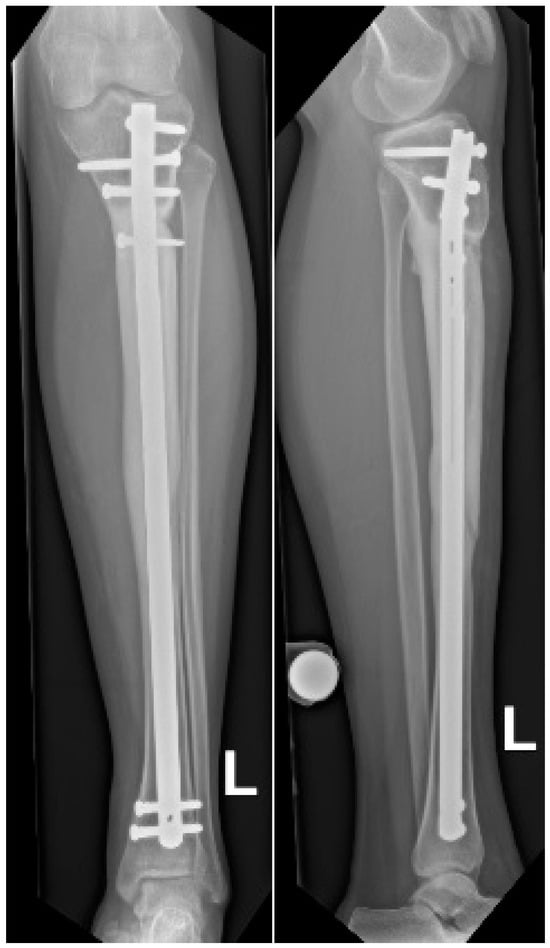

Figure 2.

Preoperative MRI of the left tibial diaphysis demonstrating an OFD/LA. (A) Hypointense lesion on T1-weighted sequence, coronal plane. (B) Hyperintense lesion on T2-weighted fat-suppressed sequence, coronal plane. (C) Hypointense lesion on T1-weighted sequence, axial plane. (D) Hypointense lesion on T2-weighted sequence, axial plane.